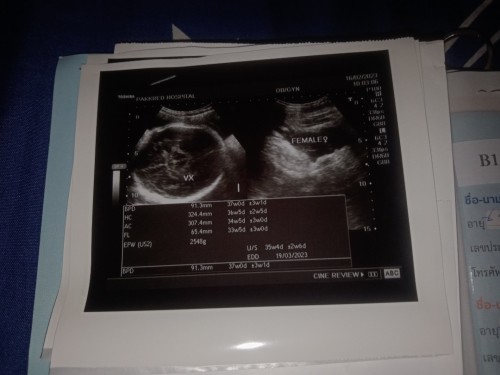

แม่บ้านนี้ 37สัปดาห์ 3วัน ยังนั่งมอไซค์ไปทำงานยุเลย เริ่มจะเดินไม่ไหวแล้ว แต่จะให้นอนยุห้องอย่างเดียวก็ปวดหลัง คิดไว้ว่าจะหยุดพักร่างกายก่อนวันผ่าสักอาทิตย์